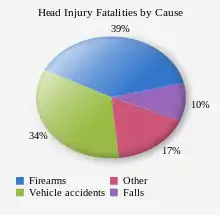

Biological, clinical, and demographic factors contribute to the likelihood that an injury will be fatal.[165] In addition, outcome depends heavily on the cause of head injury. In the US, patients with fall-related TBIs have an 89% survival rate, while only 9% of patients with firearm-related TBIs survive.[170] In the US, firearms are the most common cause of fatal TBI, followed by vehicle accidents and then falls.[165] Of deaths from firearms, 75% are considered to be suicides.[165]